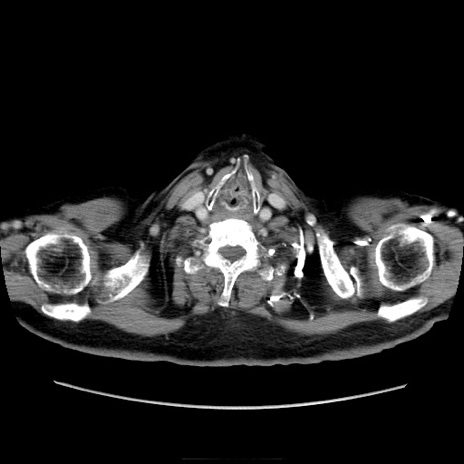

症例21(横断像)

【症例】70歳代男性

【主訴】腹痛

【現病歴】肝硬変・肝細胞癌にてかかりつけの方。約9時間前に食後より腹痛出現。症状が徐々に増悪し、嘔吐出現したため来院。

【既往歴】肝硬変、肝細胞癌(RFA、TACE後)

【身体所見】意識清明、表情苦悶様、BT 36℃、BP 129/78mmHg、P 88bpm、SpO2 97%(RA)、右上腹部から心窩部にかけて圧痛あり、反跳痛なし、筋性防御あり。

【データ】WBC 5800、CRP 0.16